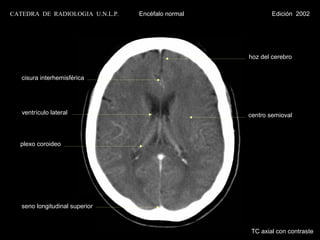

CATEDRA DE RADIOLOGIA U.N.L.P.   Encéfalo normal           Edición 2002

hoz del cerebro

cisura interhemisférica

ventrículo lateral                              centro semioval

plexo coroideo

seno longitudinal superior

TC axial con contraste